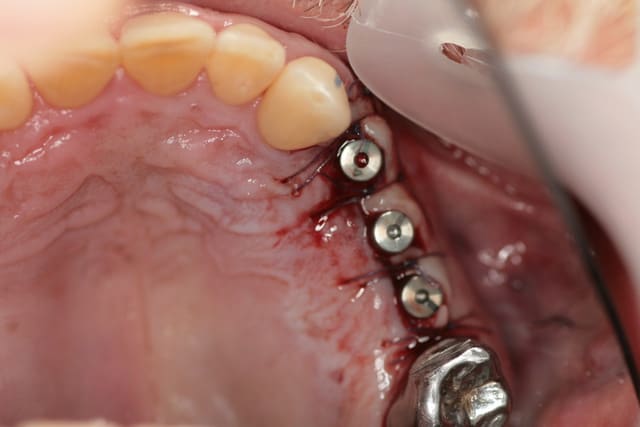

ce matin trois petits implants et mise en place des vis de cicat simultané

technique de palacci et à priori je suis assez content de moi

merci pour ton cas présentant un une chir muco implantaire dite de Palaci.

en attendant la suite, je m'y colle aussi.

ici gencive attachée déplacée apicalement autour d'un pilier implantaire lors de la mise à jour.

pour info, les implants avaient été posés après extractions , j'avais mal jaugé la future résorption osseuse...